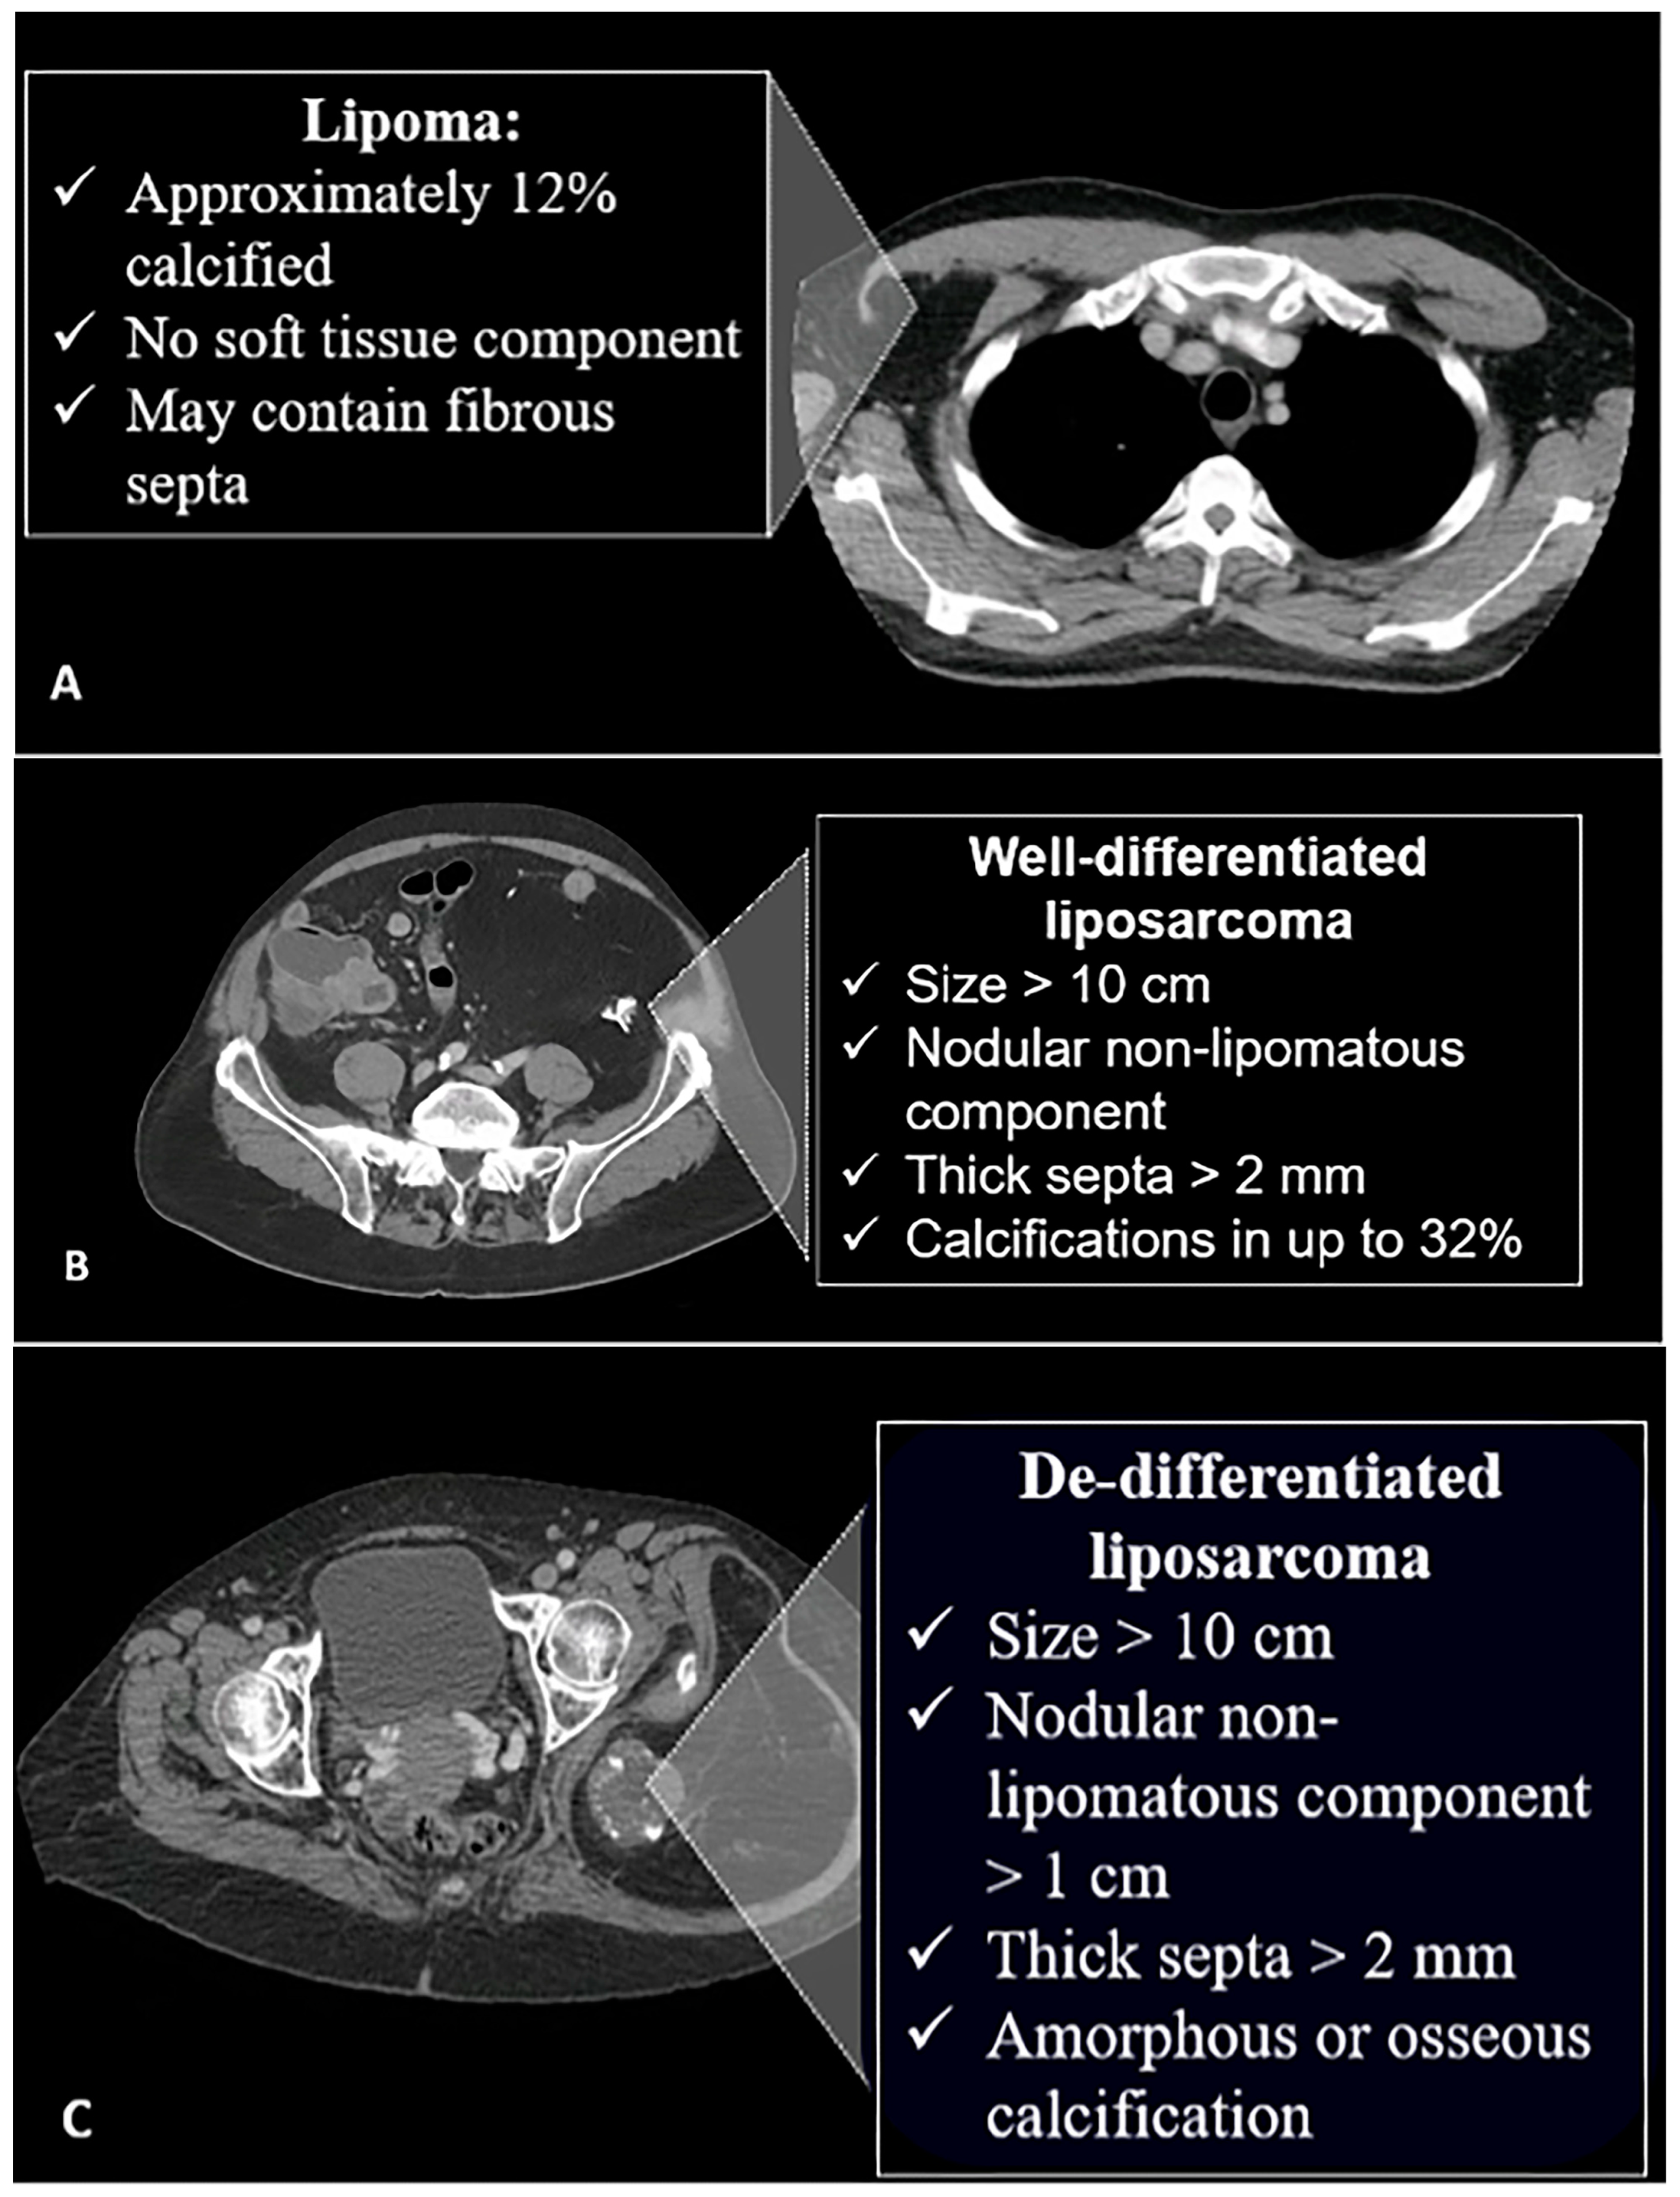

4.1. Adipocytic Tumors

- Kransdorf, M.J.; Bancroft, L.W.; Peterson, J.J.; Murphey, M.D.; Foster, W.C.; Temple, H.T. Imaging of fatty tumors: Distinction of lipoma and well-differentiated liposarcoma. Radiology 2002, 224, 99–104. [Google Scholar]

- Murphey, M.D.; Arcara, L.K.; Fanburg-Smith, J. Imaging of musculoskeletal liposarcoma with radiologic-pathologic correlation. Radiographics 2005, 25, 1371–1395. [Google Scholar]